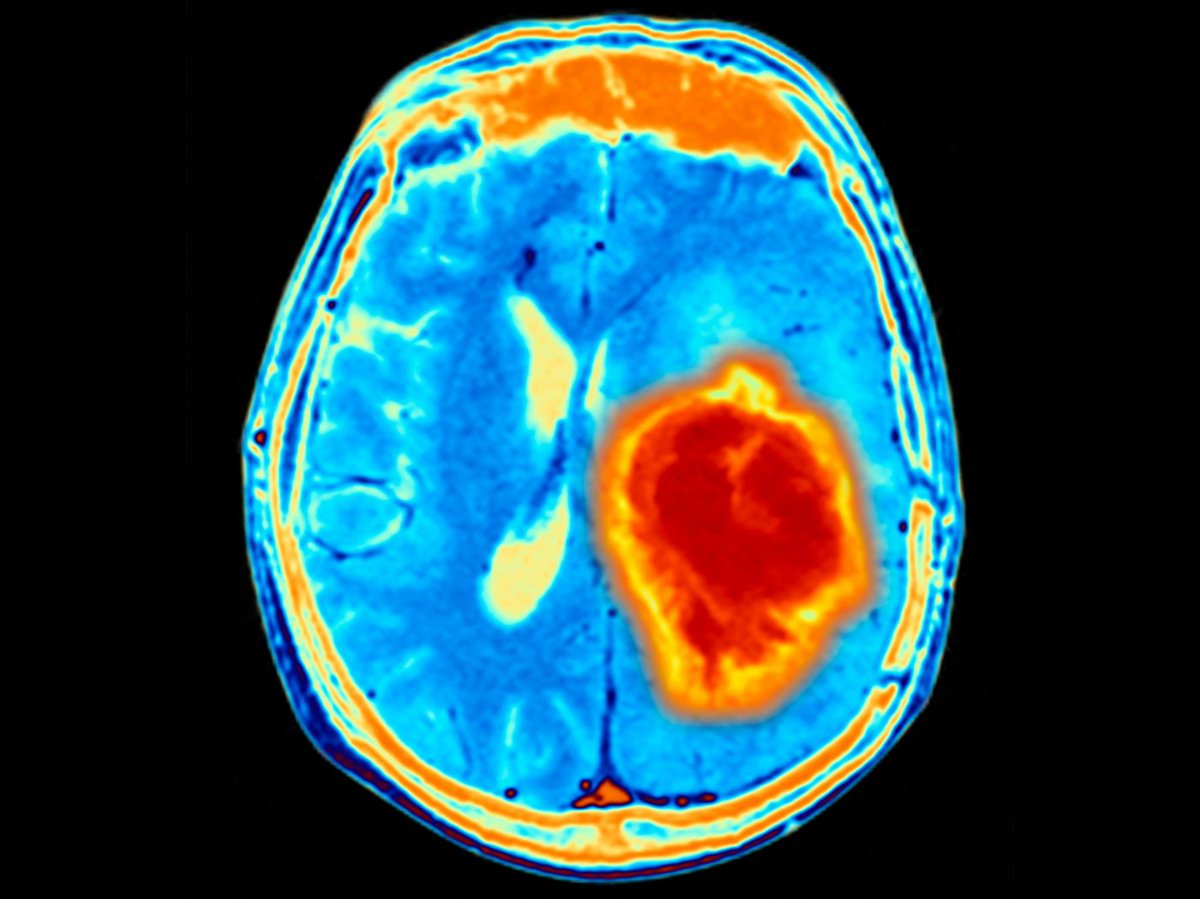

4 стадия рака головы